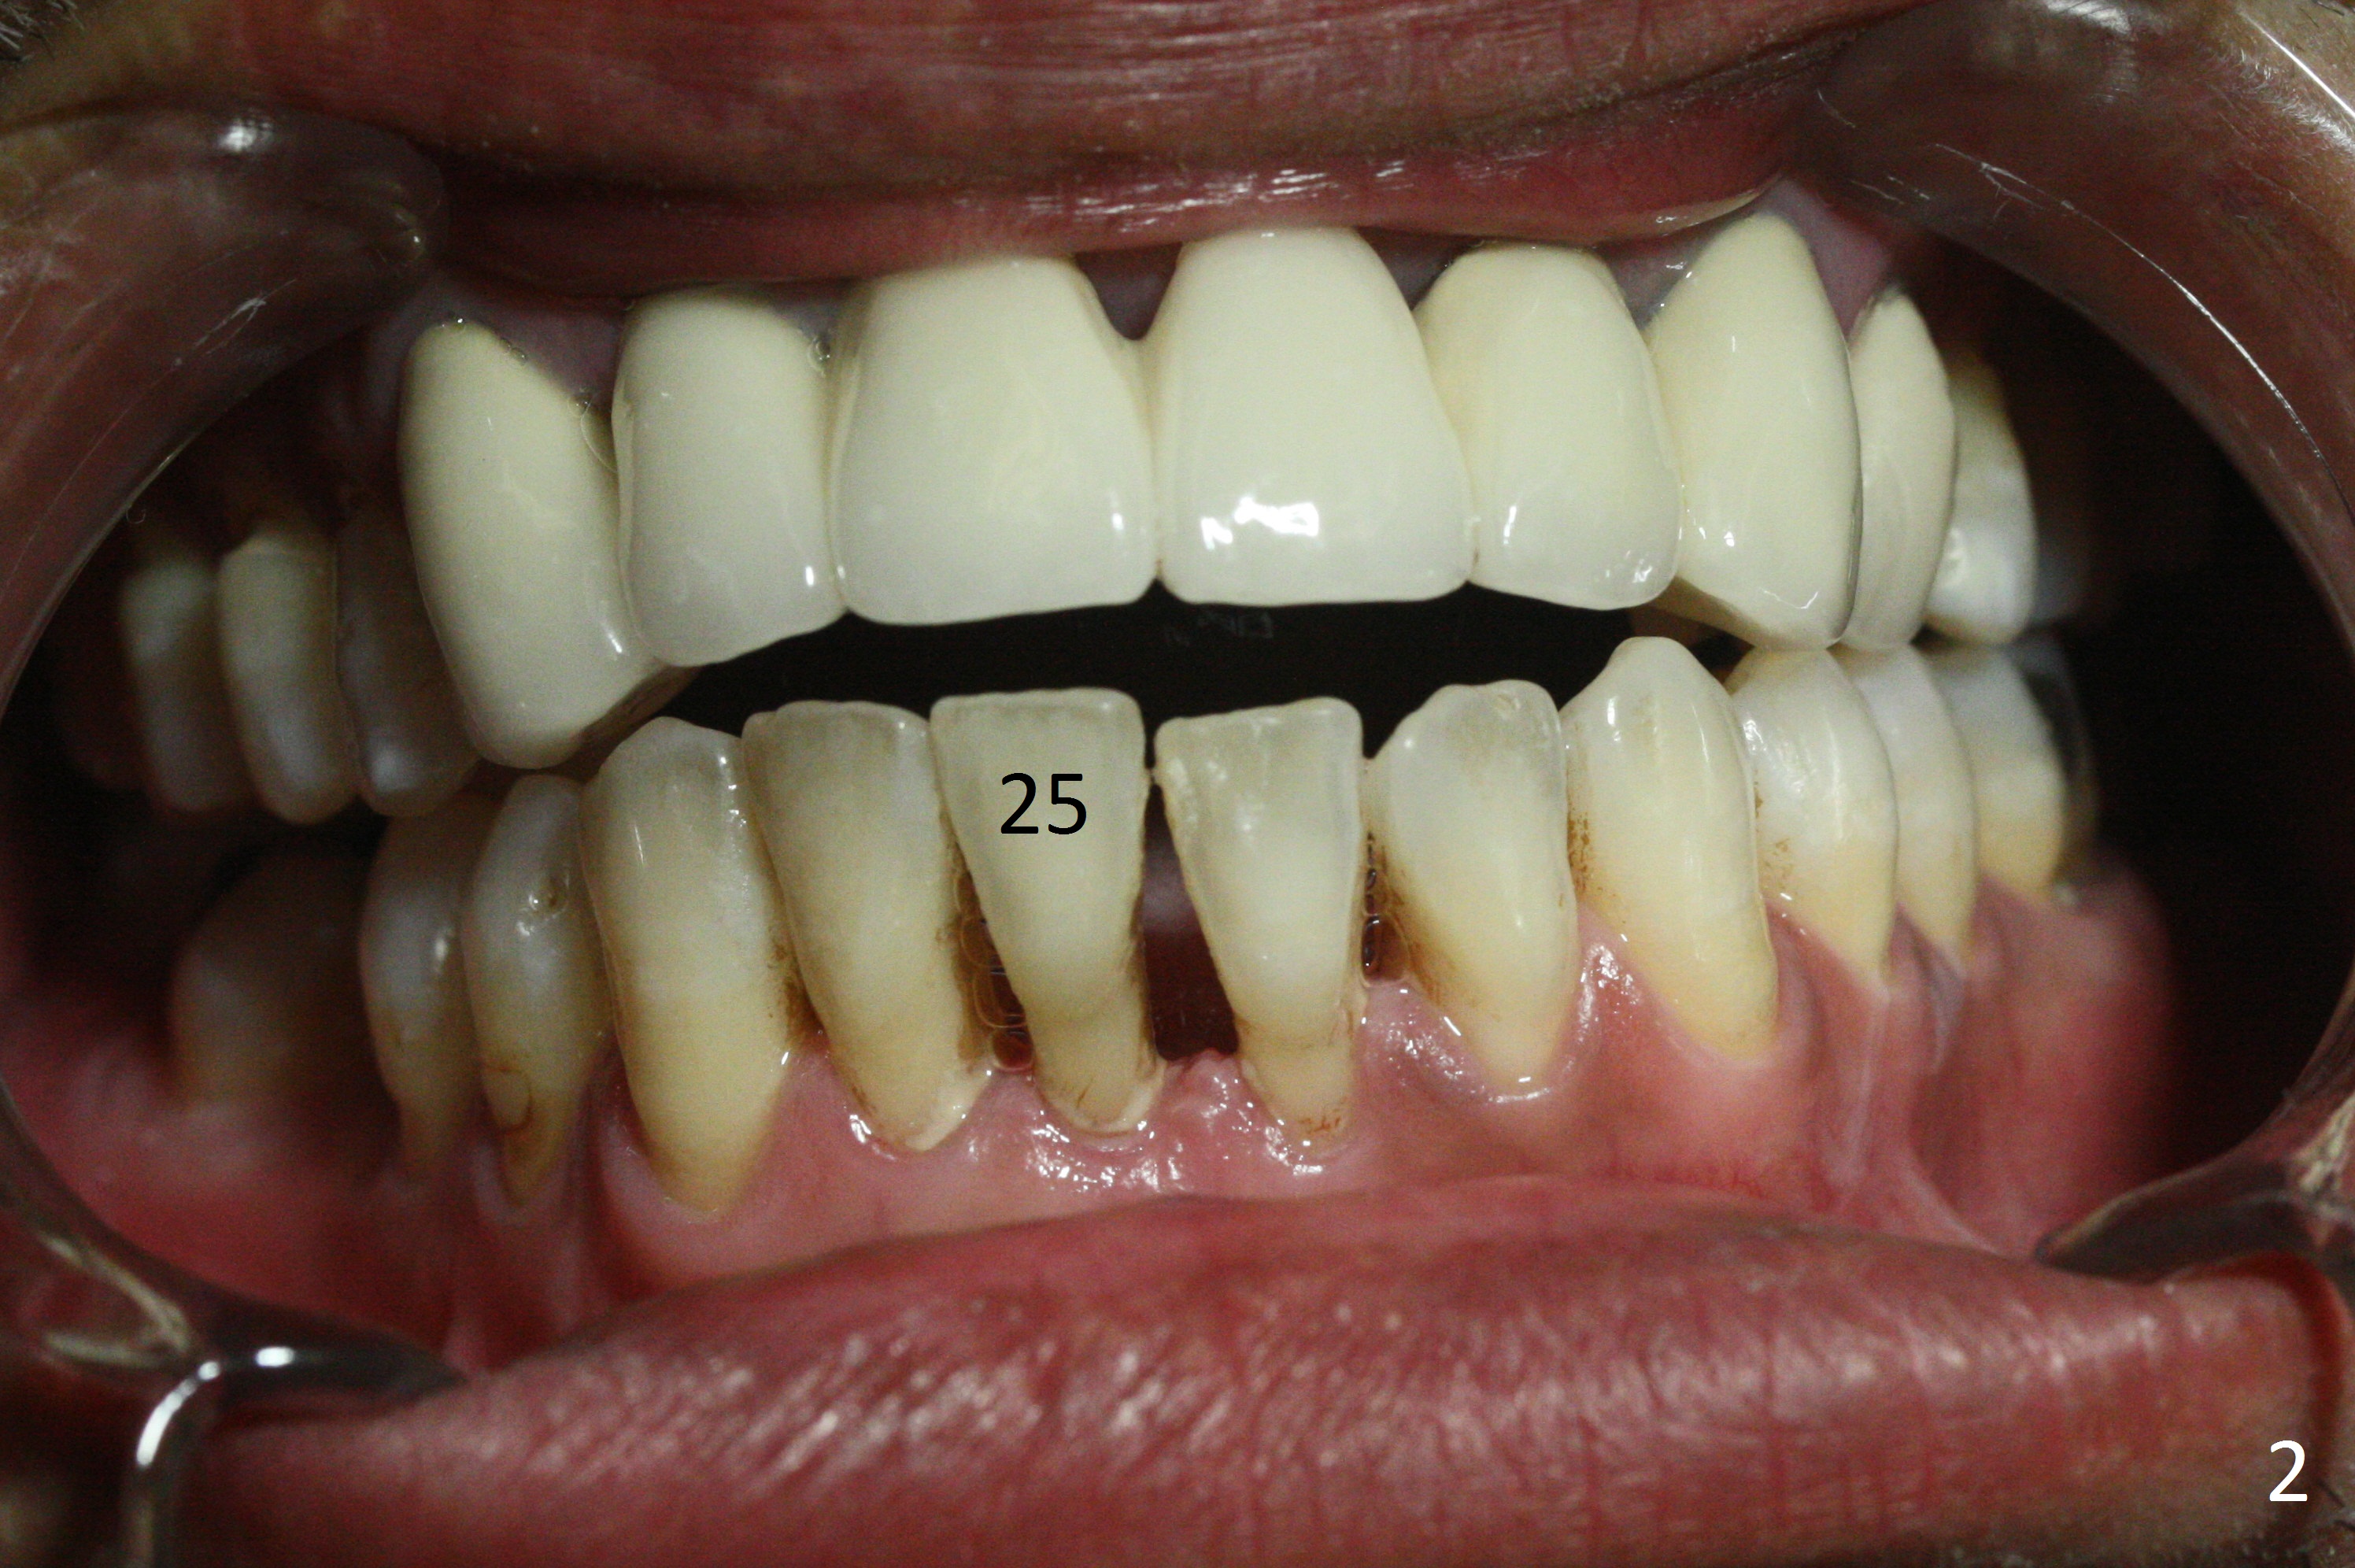

A 48-year-old man is determined to have implants for mobile teeth #14 and 25 (Fig.1). He is not pleased with the upper anterior FPD because of difficulty in cleaning. In addition to severe gingival recession (Fig.2), there is an abscess lingual to the tooth #25 (Fig.3). The latter should be associated with lingual plate defect. Osteotomy should be initiated in the center of the socket, in contrast to usual lingual starting point. A 3x16(4) mm 1-piece implant is to be placed unless the socket is small buccolingually or mesiodistally. Take PA immediately after his arrival for surgery to determine the mesiodistal width and the gingival thickness. The 2nd parameter will decide what parameter of the implant?